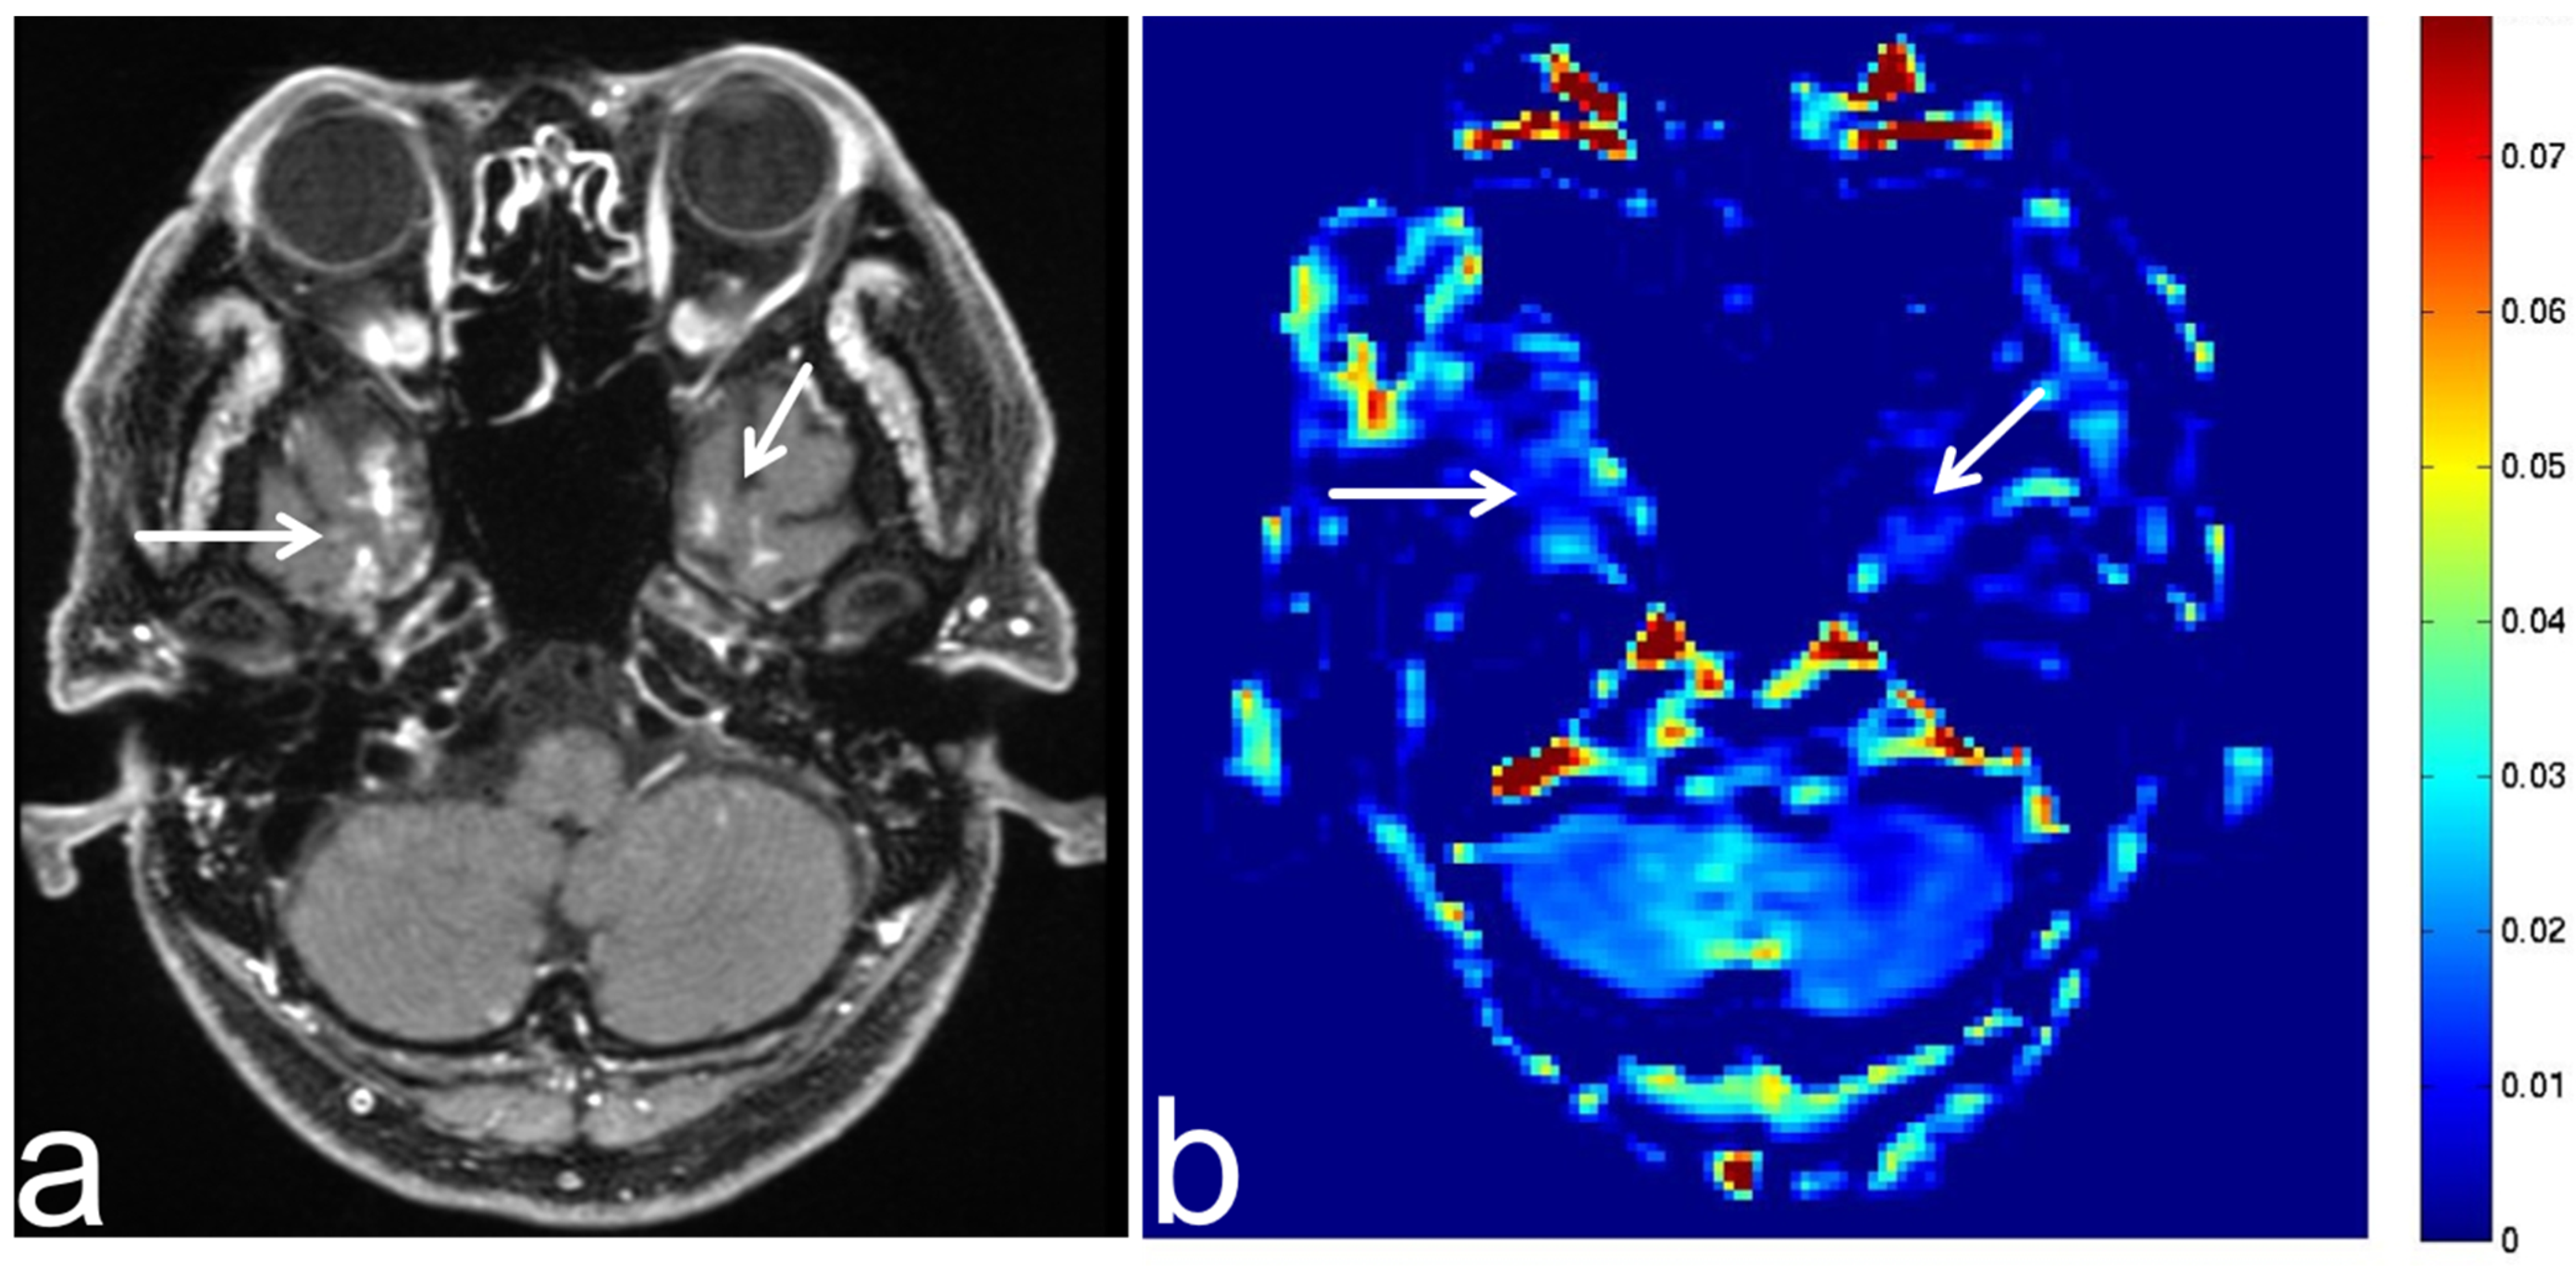

7.1. Sphenoid Sinus Mucocele

7.3. Schwannoma